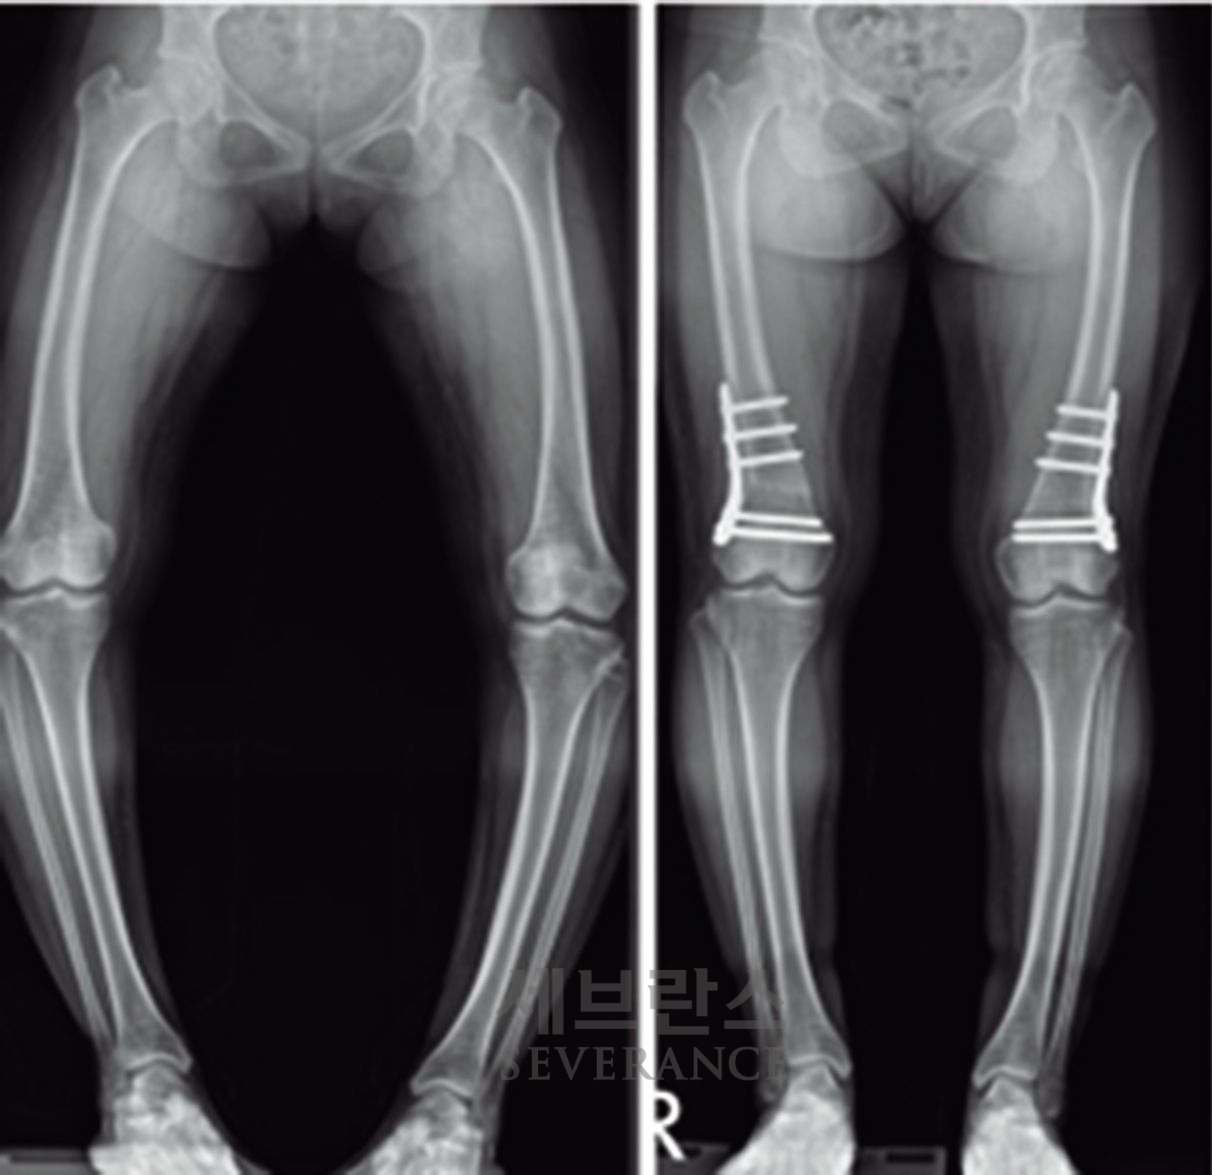

구루병으로 발생한병적 내반슬(O다리) 변형에 대해

절골 교정술을 시행한 환아